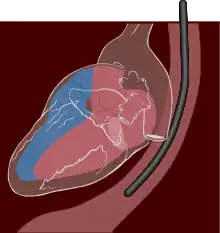

A transesophageal echocardiogram, or TEE (TOE in the United Kingdom and other countries such as Australia and New Zealand, reflecting the British English spelling transoesophageal), is an alternative way to perform an echocardiogram. A specialized probe containing an ultrasound transducer at its tip is passed into the patient's esophagus.[1] This allows image and Doppler evaluation which can be recorded. It is commonly used during cardiac surgery and is an excellent modality for assessing the aorta, although there are some limitations.[2]

TEE probes are similar in style to those used for esophagogastroduodenoscopy except the probe contains an ultrasound crystal rather than a visual camera. The ultrasound crystal images radially to the probe rather than axially (along the probe length) as the heart is not inline with the esophagus, but rather adjacent (anterior) to it.